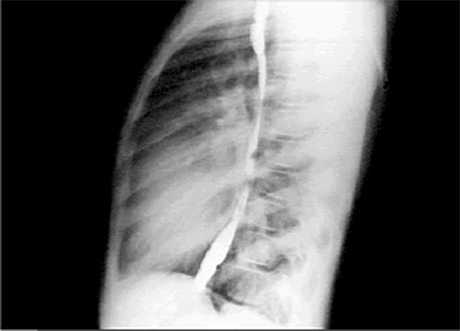

Lat

In the lateral view with barium swallow, right ventricular enlargement is manifested by obliteration of the retrosternal air space. The pulmonary arteries are large.